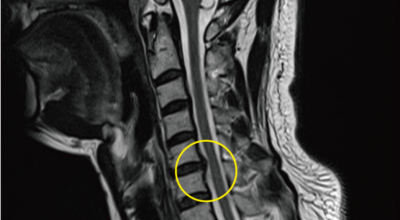

경추 사이의 추간판(디스크)이 탈출 또는 파열되어 경추신경이 자극이나 압박을 받아 통증이 생기는 증상을 말해요. 경추는 운동성이 큰 부위로 추간판이 압력을 받으면 튀어나와 척수나 신경을 압박하게 되는데요 목디스크는 퇴행성 변화 이후에 발생되기 때문에 많은 환자들이 만성적인 통증을 지니고 있는 경우가 많아요. 급성으로 생기는 경우는 교통사고, 추락, 스포츠 활동에 의한 목 부상으로 나타나기도 해요. 20대부터 가벼운 초기 증상으로 시작하여 옳지 않은 습관으로 악화되거나 호전되기를 반복해요. 나이가 들면 퇴행성 변화로 40~50대에 가장 많은 환자 수를 보인다고 합니다

목디스크는 본래의 자리에서 튀어나온 디스크의 일부 및 척추 뼈에서 생긴 골극이 양쪽 어깨, 팔, 손으로 가는 신경을 눌러 발생되는 질병입니다. 따라서 신경이 목 부위에서 훼손을 입으면 팔과 손으로 통증이 뻗어나가는 방사통이 생겨나게 되어요.

신경성형술은 목디스크 치료방법 중 비수술치료로 1mm의 초소형 카테터를 삽입하여 통증의 원인의 부위를 찾아서 신경의 유착을 풀어 주는 시술입니다. 가장 대중적으로 활용되고 있는 척추질환 비수술치료로서 신경성형술의 장점은 크게 5가지로 볼 수 있어요. 20분 이내의 짧은 시술이므로 수술에 대한 부담이 적습니다. 또 입원을 하지 않고 시술 후 일상생활이 바로 할 수 있는 것이 장점이예요.